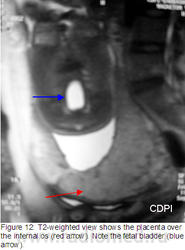

Клиника де Diagnóstico пор Imagem (CDPI), Институт Fernandes Figueira (IFF) - FIOCRUZ